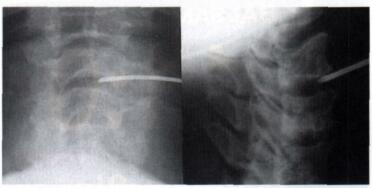

tmpA102-1.jpg

Minimalinvasivität - nur über eine Kanüle wie hier an der Halswirbelsäule erkennbar wird der Eingriff ausgeführt